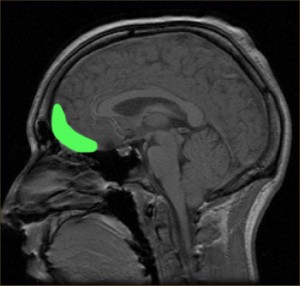

Ubicación de la corteza orbitofrontal. Imagen: Paul Wicks (DP).

La resonancia magnética encontró que tenía un tumor cerebral, un hemangiopericitoma del tamaño de un huevo en la corteza orbitofrontal derecha, la zona situada en la región más anterior e inferior del hemisferio cerebral derecho, por detrás de la cuenca del ojo derecho.

La corteza orbitofrontal es una de las regiones cerebrales donde puede producirse bastante daño sin que apenas se note, sin que el paciente piense que debe ir al médico o incluso yendo, sin que el médico sospeche que algo anda mal. Esta región cerebral está relacionada con el juicio crítico, el control de los impulsos, la toma de decisiones y el comportamiento social. La corteza orbitofrontal se encarga de inhibir las acciones inapropiadas, vetando el impulso emocional inmediato que supone la obtención de placer y sustituyéndolo por una respuesta acorde a nuestra educación, a nuestras convenciones sociales, integrada con aquello que consideramos moralmente admisible y que nos permite seguir siendo un miembro aceptado en la sociedad.

Las personas con una lesión en la corteza orbitofrontal en la infancia tienen problemas para la adquisición de los principios morales y sociales y normalmente muestran un juicio pobre, poco control de los impulsos y sociopatía. Esta sociopatía normalmente se refleja en una tendencia a los comportamientos violentos, la ausencia de remordimientos o culpa, dar poco valor a las leyes, a las normas sociales y a los derechos de los demás y dificultades para mantener un trabajo. Son personas que a menudo viven en los márgenes de la sociedad. Si cometen algún crimen suele ser al azar y de forma espontánea y no planificada. Cuando la lesión ocurre en la vida adulta, sin embargo, se ve también sociopatía, pero el desarrollo moral establecido previamente se mantiene.